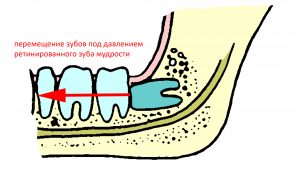

Несмотря на то, что зуб еще не прорезался, он уже влияет на зубной ряд. Он может вызвать перемещение зубов и формирование скученности в переднем отделе: